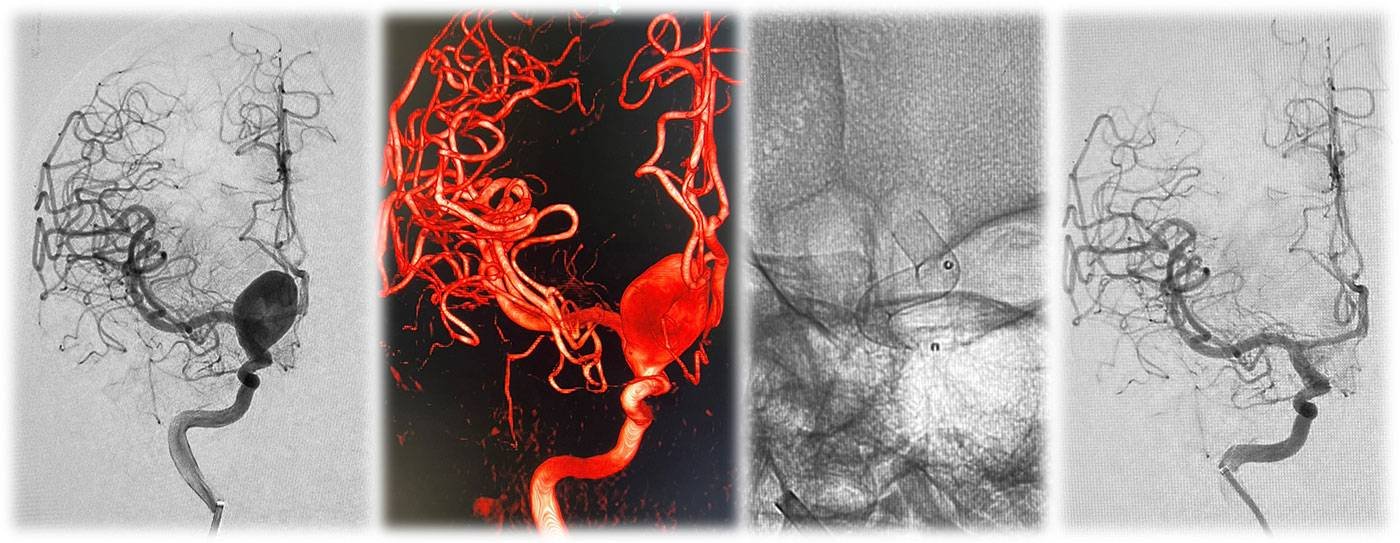

A term, appropriate-for-gestational-age neonate with normal APGAR scores and no history of perinatal hypoxia presented with seizures on day 2 of life.